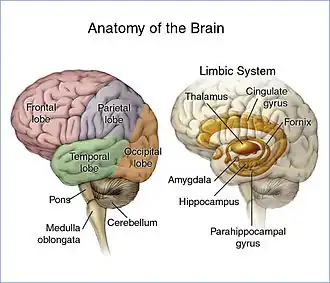

The brain is divided into lobes and each lobe or area has its own function.[18][19] A tumour in any of these lobes may affect the area's performance. The symptoms experienced are often linked to the location of the tumour, but each person may experience something different.[20]

- Frontal lobe: Tumours may contribute to poor reasoning, inappropriate social behavior, personality changes, poor planning, lower inhibition, and decreased production of speech (Broca's area).[20]

- Temporal lobe: Tumours in this lobe may contribute to poor memory, loss of hearing, and difficulty in language comprehension (Wernicke's area is located in this lobe).[19]

- Parietal lobe: Tumours here may result in poor interpretation of languages, difficulty with speaking, writing, drawing, naming, and recognizing, and poor spatial and visual perception.[21]

- Occipital lobe: Damage to this lobe may result in poor vision or loss of vision.[22]

- Cerebellum: Tumours in this area may cause poor balance, muscle movement, and posture.[23]

- Brain stem: Tumours on the brainstem can cause seizures, endocrine problems, respiratory changes, visual changes, headaches and partial paralysis.[23]

- Leptomeninges: Tumours that spread to the leptomeninges, the lining of the brain, may cause cranial nerve palsies such as facial paralysis, abnormalities of eye movement, abnormalities of facial sensation or swallowing difficulty, depending on which cranial nerves are involved.[24]